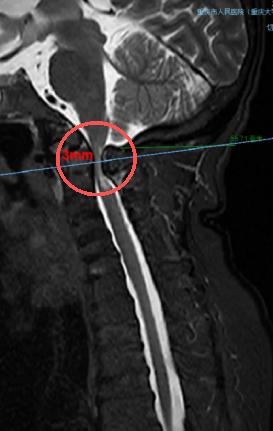

術(shù)前,頸椎MRI顯示,患者脊髓嚴(yán)重受壓(圓圈處)。重慶市人民醫(yī)院(重慶大學(xué)附屬人民醫(yī)院)供圖